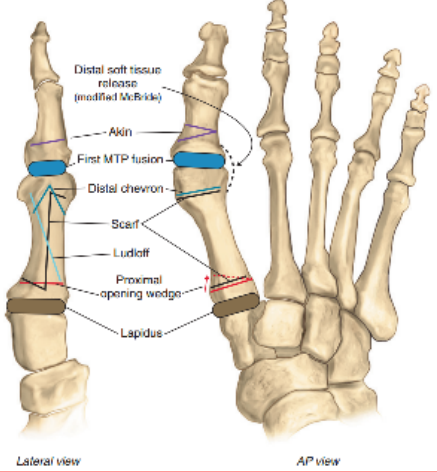

21 前足—拇外翻

拇外翻角Hallux valgus angle,HVA(metatarsophalangeal angle,MTP-1)

正常 < 15°

轻度 < 20°

中度 20°~40°

重度 > 40°

第一、二跖骨间角Intermetatarsalangle,IM 1-2

正常 < 9°

轻度 9°~11°

中度 11°~16°

重度 > 16°

跖骨远端关节角(DMAA)正常<8°